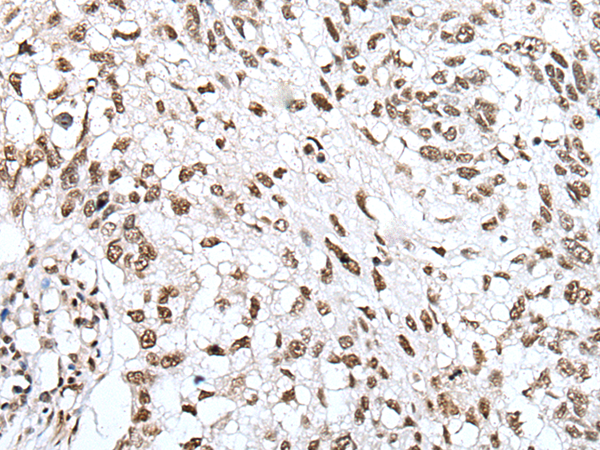

IHC positive control: |

Human lung cancer and human brain |

IHC Recommend dilution: |

25-100 |